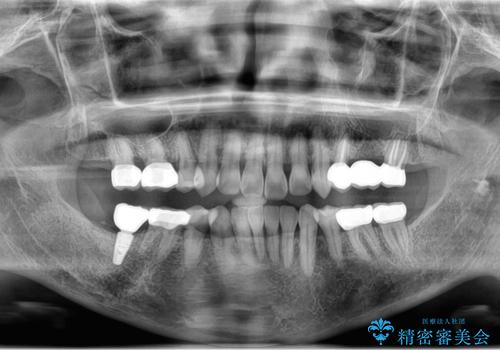

X線、歯周組織検査の結果、全体的に奥歯には重度〜中等度の歯周病の問題が見られました。

残すことのできない歯、予後の悪い歯を抜去し、ブリッジイ・ンプラントによる機能回復をおこなっていくと同時に、残すことのできる歯には歯周病治療をしっかりと行い、

将来に渡りしっかりと自分の歯で噛めるような口腔内環境を構築していきます。

においやぐらつきなどの深い症状がなくなり、しっかりと噛めるようになった!と喜んでいただくことができました。